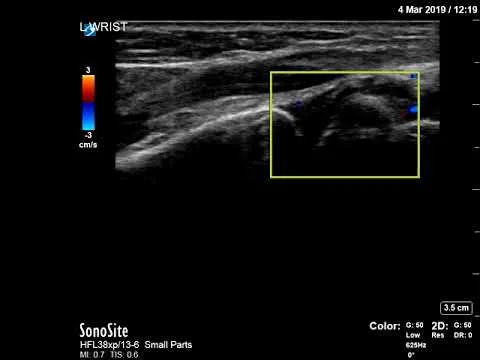

Synovial thickening R wrist